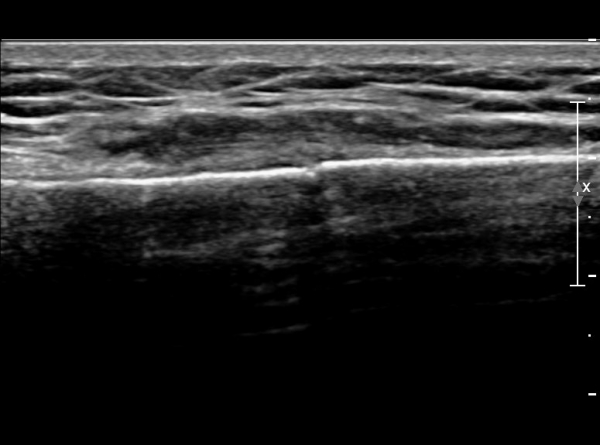

Á¶±Ý ´õ ¸»´ÜÀ¸·Î À̵¿ÇÏ´Ï Äá¾Ë»À ÇÇÁú°ñ ¿¬¼Ó¼º ¼Ò½ÇÀÌ °üÂûµÊ(»çÁö 3),